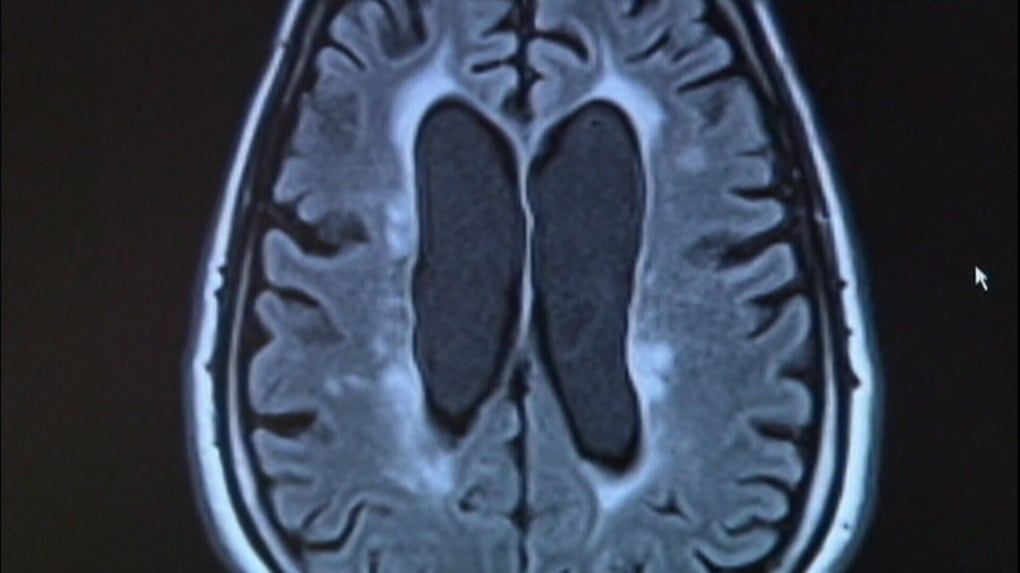

CTE found in brain of 25-year-old football player plagued by concussions